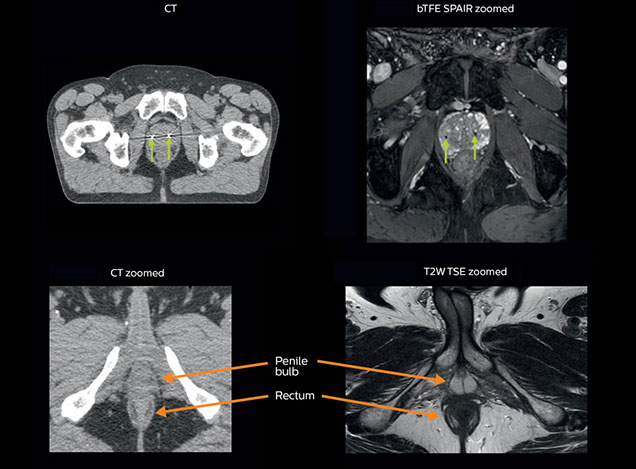

A 63-year-old patient with prostate cancer, cT3bNxM, Gleason 7, underwent MRI on Ingenia 3.0T MR-RT before radiation therapy.

Intraprostatic lesions are visible on the bTFE MR image, but not on the CT image. MRI shows excellent soft-tissue contrast for the visualization of critical structures like the rectum and penile bulb.

Fiducial markers (green arrows) are used in registration of MR images to CT, to transfer the MR-based delineations onto the CT image dataset.